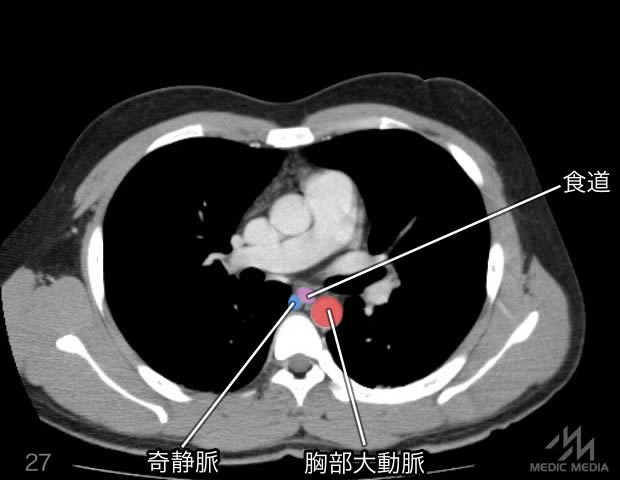

造影CT

スライド(画像下)を動かしながら,CTで臓器の位置を確認してみましょう.

消化器